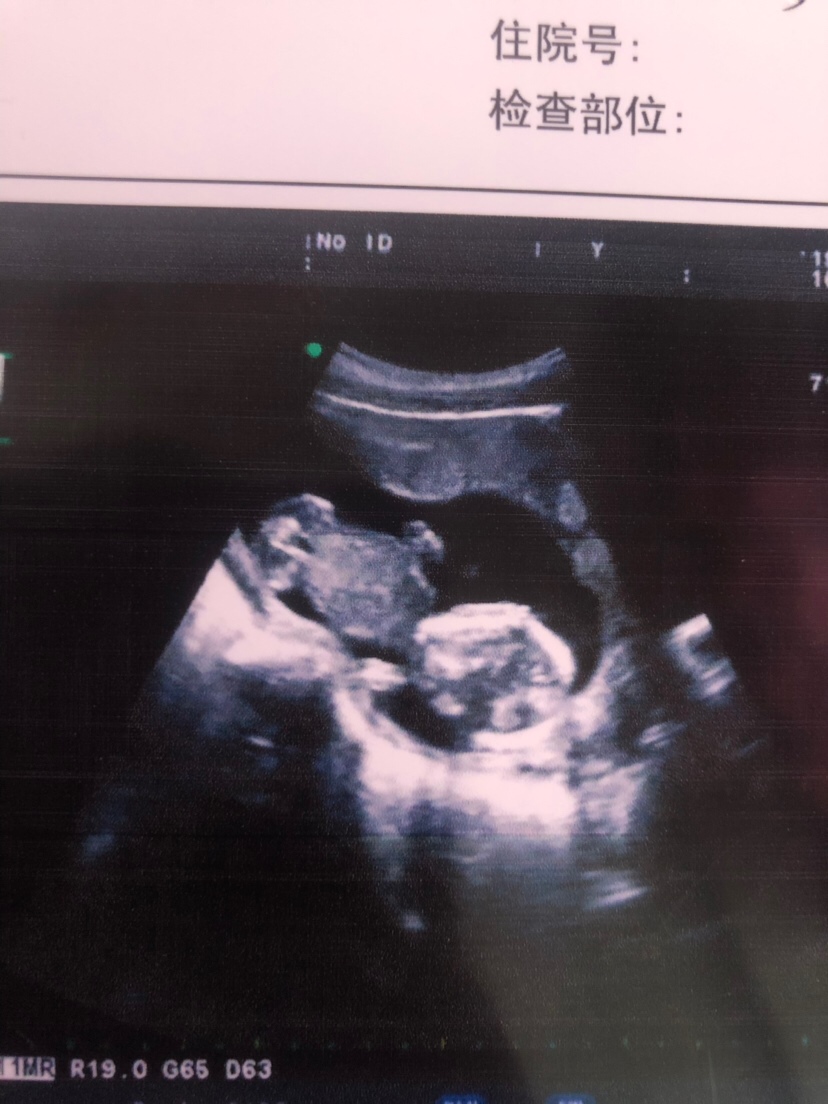

孕11周+0天

十六周呀,我才是十一周快熬不下去了 😢

💭在当地较为美貌的人:我10周已经难受的不行了